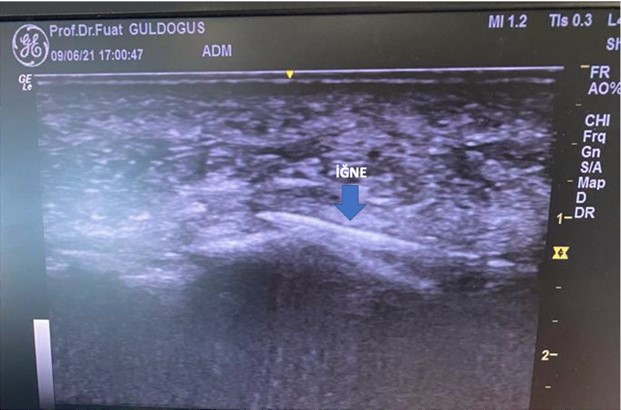

Ozon Uygulamalarında Ultrasonografi ve Skopi Kullanımı